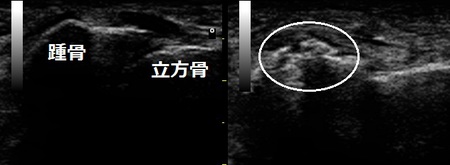

右足関節 左足関節患部

川越市 主婦 左足関節の痛み、二分(踵立方)靭帯付着部裂(剥)離骨折。

超音波検査を行ったところ、二分(踵立方】靭帯付着部の骨剥離が認められました(画像丸の中)。

アイシング後、剥がれた骨を元の場所に戻し固定しました。

固定はテーピングとサポーターでしっかりと固定します。テーピングは毎日取り換えるので、固定にゆるみが

出ず、腫れの消失も早くなります。1週間後には犬の散歩も可能となりました。